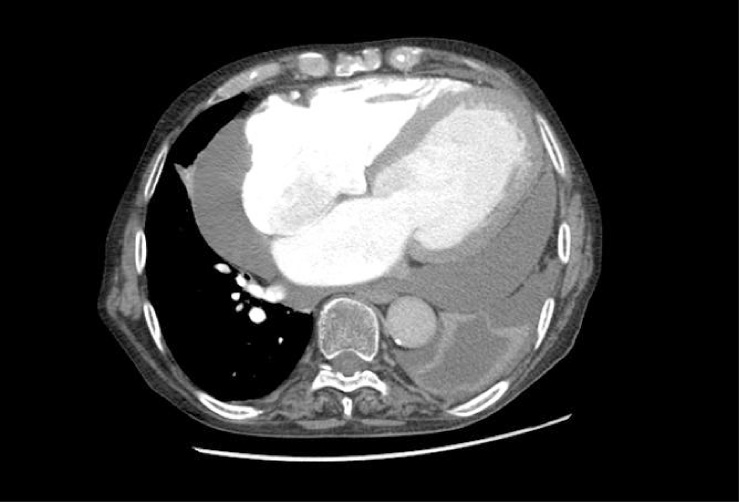

L’ecocardiogramma trans-toracico mostrava FE = 28%, versamento pericardico prevalente a carico della parete libera del ventricolo sinistro e posteriormente, con scollamento massimo di 4 cm, senza segni di tamponamento; discreto aumento della pressione arteriosa polmonare (PAP) a 45-50 mmHg. Dalla TAC torace erano visibili cardiomegalia, abbondante versamento pericardico, discreto versamento pleurico a sinistra con atelettasia parziale del lobo inferiore, alterazioni parenchimali bilaterali con aspetto a vetro smerigliato e qualche linfonodo mediastinico con diametro < 1 cm (Figure 4 e 5).

Figura 4. TAC torace (aprile 2012): cardiomegalia, abbondante versamento pericardico, discreto versamento pleurico a sinistra con atelettasia parziale del lobo inferiore, alterazioni parenchimali bilaterali con aspetto a vetro smerigliato, qualche linfonodo mediastinico con diametro < 1 cm

Figura 5. TAC torace (aprile 2012): particolare per il parenchima polmonare